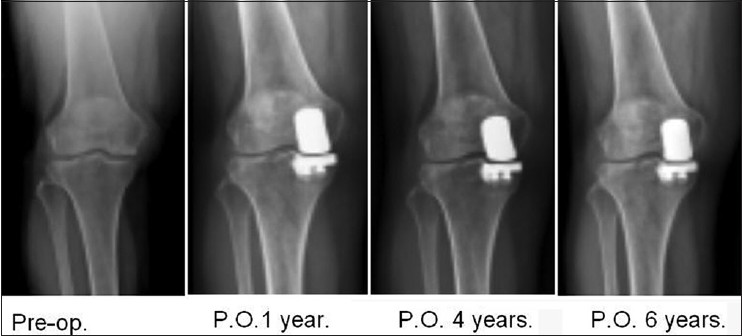

Functional outcomes of uni-knee arthroplasty for medial compartment knee arthropathy in asian patients

p. 406

To Wong, Ching-Jen Wang, Jun-Wen Wang, Jih-Yang Ko DOI:10.4103/2319-4170.132877 PMID:25179698

Background: Uni-knee arthroplasty (UKA) has shown better knee kinematics and motion that may better suit the activities of daily living in Eastern countries. The purpose of this study was to evaluate the functional outcomes of UKA for medial compartment knee arthropathy in Asian patients.

Methods: The study cohort consisted of 48 patients with 51 UK A knees. Only one type of prosthesis was used and all components were cemented. Postoperative management included ambulation with weight bearing, range of motion, and muscle strengthening exercises as tolerated until full recovery. The average follow-up was 52.0 ± 24.0 (range 12-92) months. The evaluation included functional assessment, the Knee Society knee and functional scores, the International Knee Document Committee (IKDC) subjective and objective scores, and radiographs of the knee.

Results: The overall clinical outcomes of the knee showed the functional outcome of the knee to be normal in 51%, nearly normal in 37%, abnormal in 8%, and severely abnormal in 4%. The functional activities included stair climbing in 96%, squatting in 76%, jogging in 71% and kneeling in 47%. Three-quarters of the patients were able to kneel for daily activities. Approximately 98% of the patients were satisfied with the operation. The survivorship of the prosthesis was 98% with one revision pending. Radiographic evaluations revealed the components were centered in 82% and off-centered in 18%. Osteoarthritis was 22% preoperative and 27% postoperative for the patellofemoral compartment, and 0% before and 4% after surgery for the lateral compartment. The functional outcomes showed no difference between patients with and without patellofemoral arthritis. The complications included one component malposition and one knee pain of undetermined origin.

Conclusions: UKA provides excellent pain relief and restoration of knee function including kneeling, squatting, and sit-to-stand activities that perfectly fit the oriental lifestyle and high patient satisfaction in Asian patients at medium-term follow-up. The complications were rare and the survival rate was 98% at medium-term follow-up.